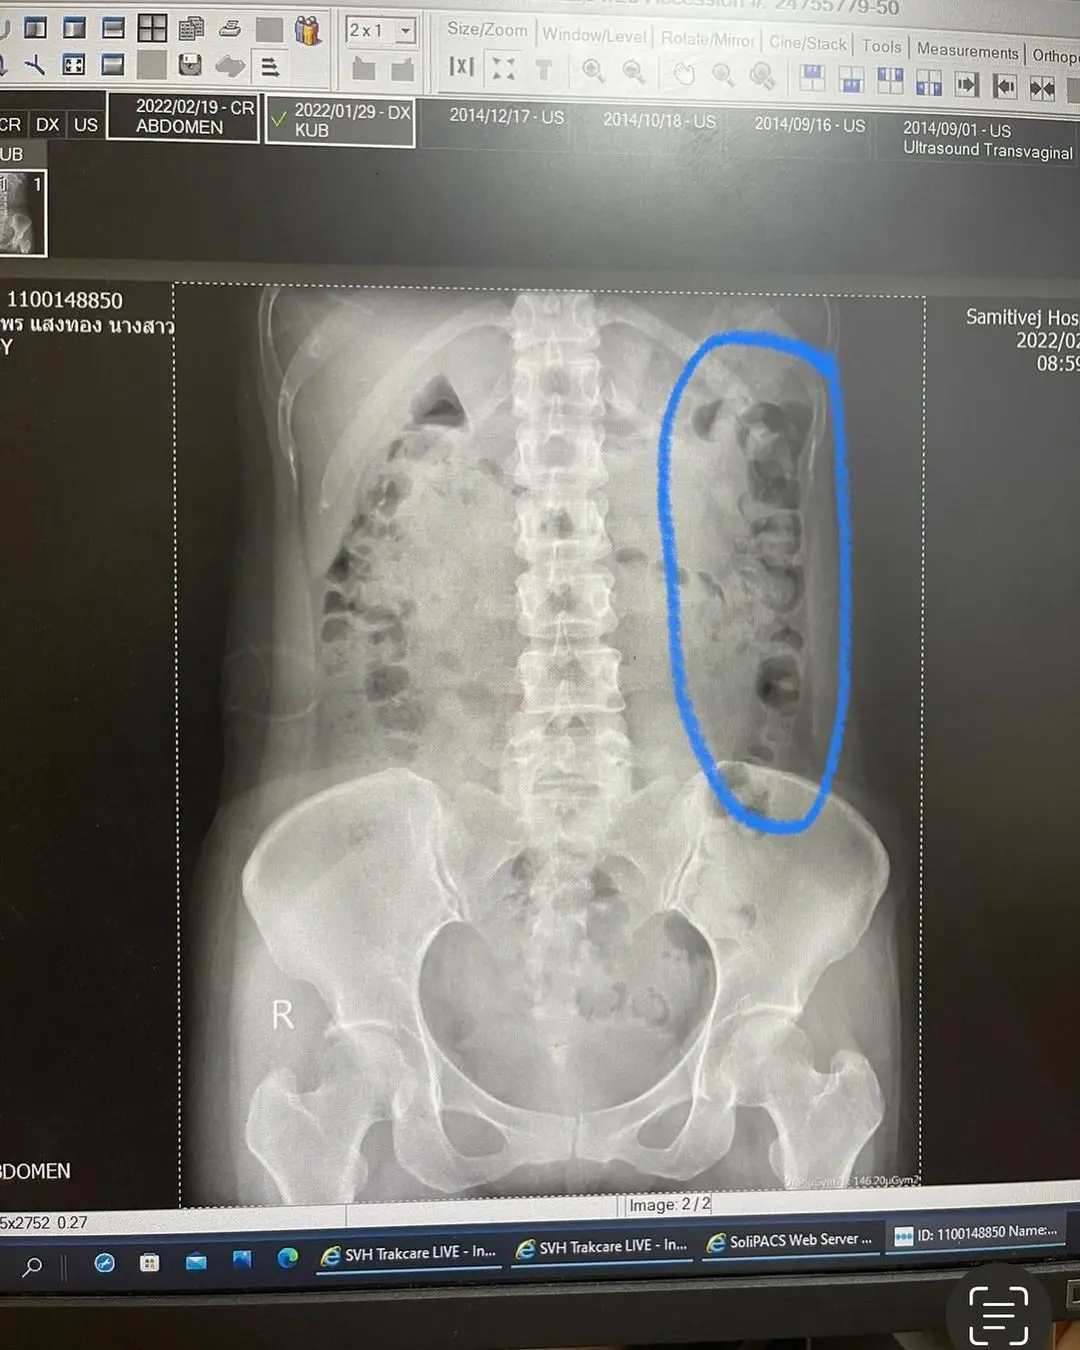

– วันนี้ขอคุณหมอเอกซเรย์ดูอีกรอบ มั่นใจมาก ว่าหายไปเยอะแน่ ๆ ปรากฏว่า “ยังเยอะอยู่จ้าาาาา” หมอบอก คุณจมาพร มันยังเยอะอยู่เลยครับ แต่ที่เราเห็นสีน้ำเงินที่วงไว้ทางขวามือของทุกคน คือมันก็อัดแน่นน้อยลง แต่หมอยังย้ำว่า “เยอะอยู่จ้าาาา”

– หมอบอก กินต่อไปอีกหลาย ๆ เดือนเลยจ้ะคุณจมาพร น่าจะยาว ๆ ไป

ก็สรุปว่า มันยังเยอะอยู่นาจาา ก็รักษากันต่อไป หมอน่ารักมาก บอกว่า ซื้อยาที่ให้กินเองก็ได้คุณจมาพร สรุปก็คือ เสียแต่ค่ารักษา กับเอกซเรย์ ค่าเสียหาย 1,000 บาทถ้วน ไอเลิฟมากกก